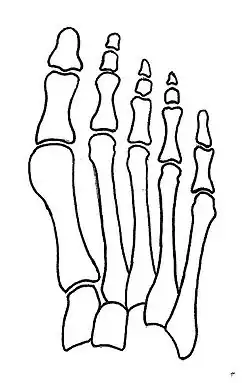

Primus varus deformity

Primus varus deformity is the leaning of the first metatarsal bone away from the second metatarsal and towards the opposite foot (Fig. 1). As it leans over, its head sticks out to form the bunion bump and it also widens the forefoot to cause shoes feeling too tight. Thus when bunion pain becomes unmanageable, surgical correction is to narrow the forefoot by repositioning of the first metatarsal head back to its normal position. This can be done by osteotomy (bone-breaking), soft tissue (non-osteotomy) or fusion techniques.